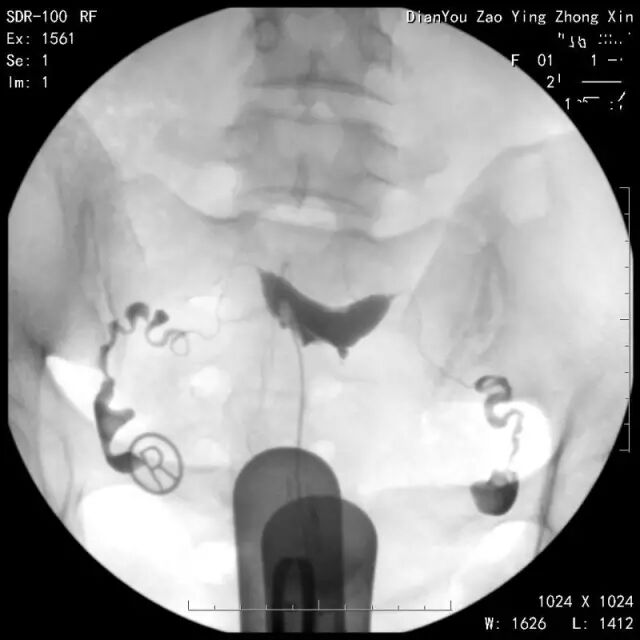

那么一张标准合格的碘水造影片长什么样呢?一起来看一组图片吧。

↑第一张:清楚地显示正常的宫腔形态。

↑第二张:显示有碘水充盈双侧输卵管腔。

↑第三张:可见碘水自伞端流出。

↑第四张:延迟涂抹片,可见碘水在盆腔内均匀涂抹。(这张非常重要,如果做了造影却没有延迟涂抹片,造影可以说白做了,无法正确做出诊断,基本靠猜,你没看错,靠猜!)